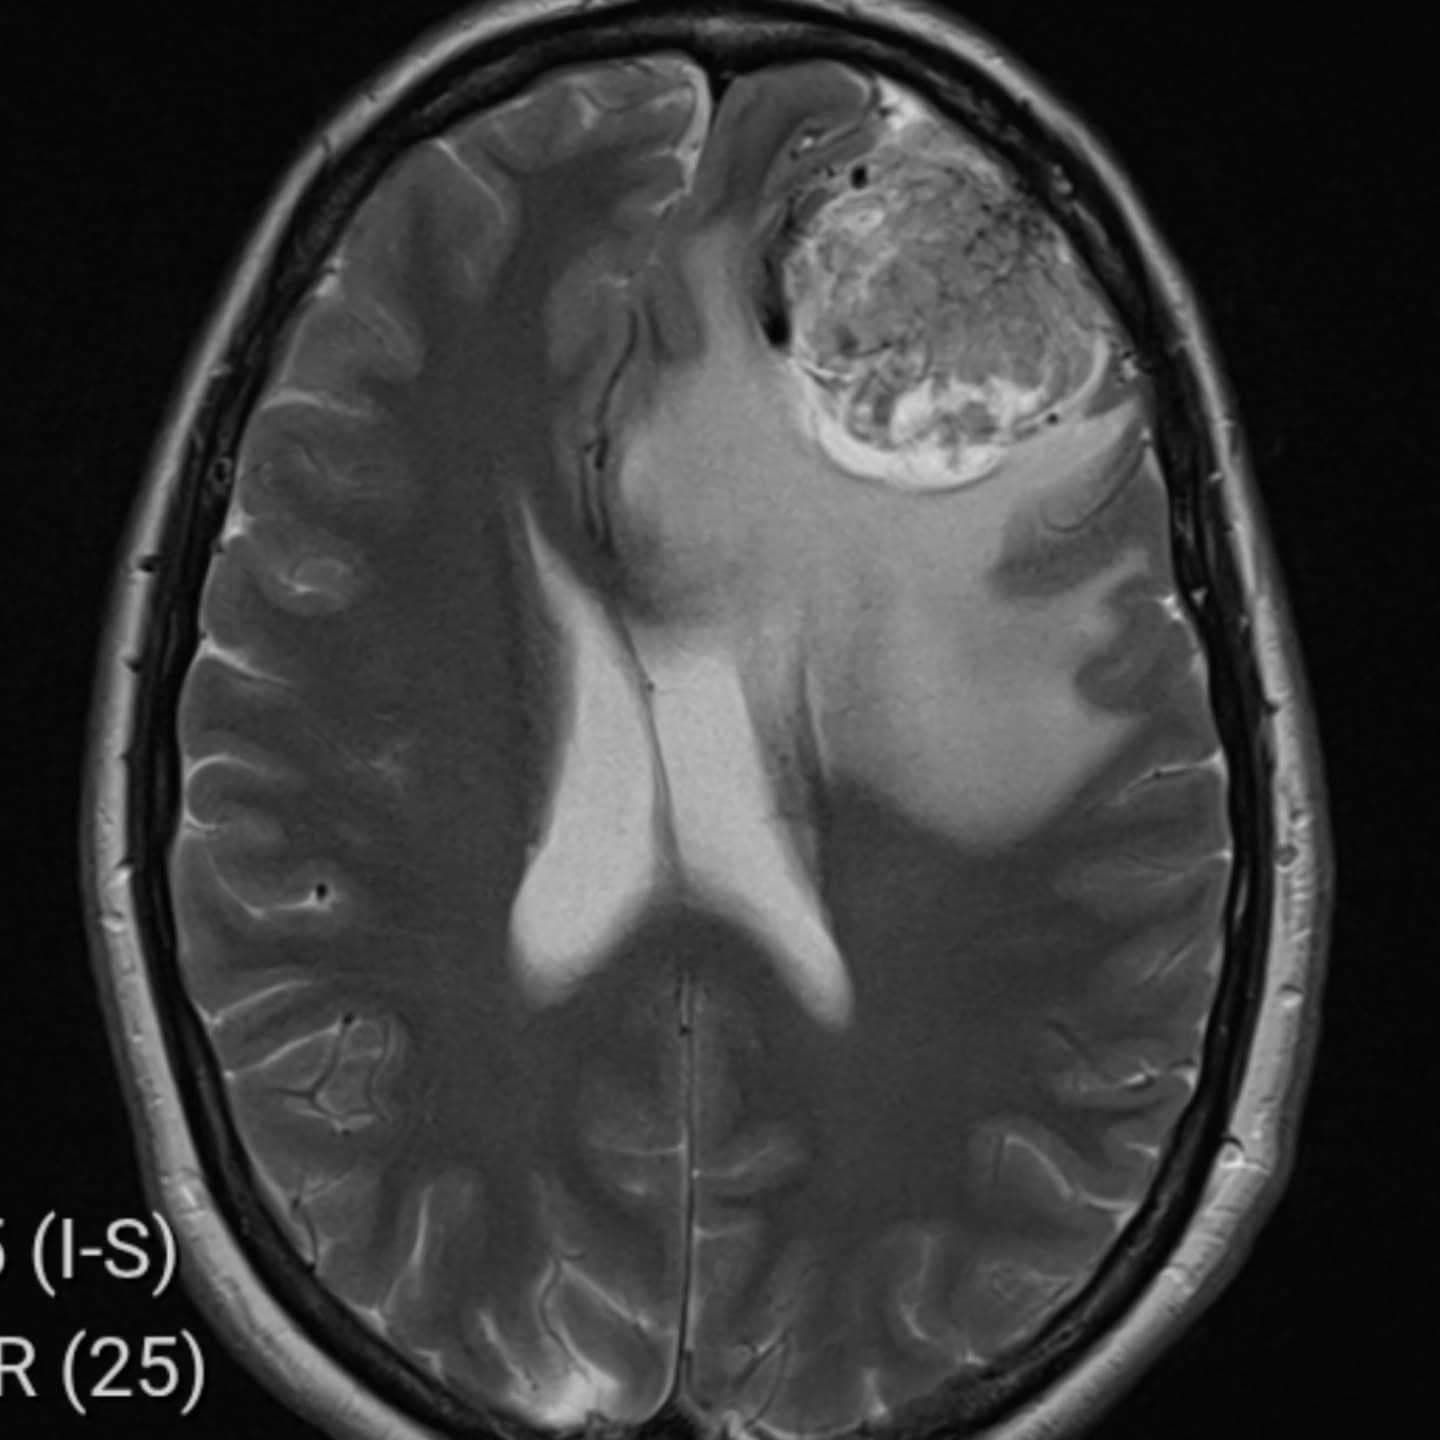

Šokujúca diagnóza

Výsledok prišiel už o pár hodín. Lekári ju okamžite poslali na urgentné oddelenie nemocnice v Medway, kde jej diagnostikovali rozsiahlu masu v čelovom laloku. Neskôr sa potvrdilo, že ide o meningeóm – nezhubný nádor mozgu. „Zrútila som sa, keď mi to povedali. Dlho trvalo, kým som sa vôbec dostala k správnej diagnóze,“ uviedla Nikita. V apríli 2025 podstúpila na londýnskej klinike King’s College Hospital štvorhodinovú operáciu, počas ktorej jej lekári nádor úplne odstránili. Zákrok prebehol práve v deň 40. narodenín jej manžela. „Ja som bola pokojná, ale pre rodinu to bolo omnoho ťažšie,“ dodala.